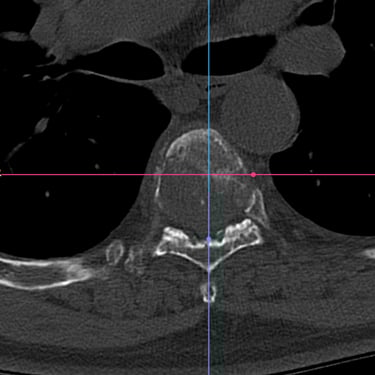

🧠 Cirugía de Revisión Cervical: Estabilidad Posterior en Seudoartrosis y Enfermedad del Segmento Adyacente.

La seudoartrosis cervical con subsidencia del cage y enfermedad del segmento adyacente genera dolor e inestabilidad. La artrodesis cervical posterior con tornillos a masas laterales y pediculares es una técnica eficaz para lograr una fijación sólida, mejorar la estabilidad y aliviar los síntomas neurológicos.